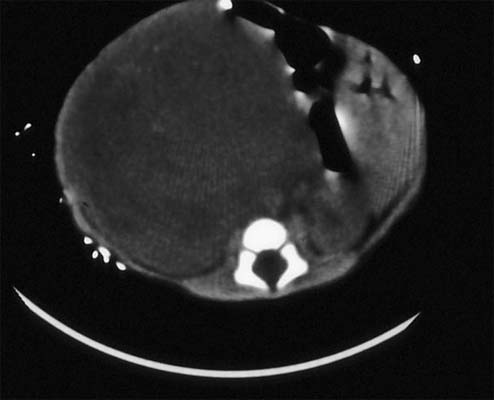

Tumeur de Wilms